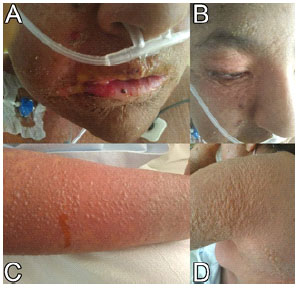

Evolution. Two days after admission, the patient presented fever, hypotension, and an episode of generalized tonic-clonic seizures. Mucocutaneous sloughing and multiple blisters with positive Nikolsky and Asboe-Hansen sign were evidenced. (Figure 3), and methylprednisolone 1 gram every 24 hours IV, piperacillin/tazobactam 4.5 grams every 6 hours IV, vancomycin 1 gram every 12 hours IV, and norepinephrine 0.1 μg/kg/min were started. Skin detachment was maximum on the third day after admission (Figure 4). On the fifth day after admission, improvement of the lesions was evidenced (Figure 5), she tolerated withdrawal of vasopressor and oxygen. The result of the skin biopsy showed lichenoid-interface dermatitis, apoptotic keratinocytes, subepidermal blisters, spongiosis, basal vacuolation and perifollicular lymphocytic infiltrate, compatible with TEN. Based on the causal assessment of TEN, 500 mg valproate was reinitiated every 12 hours orally. The patient evolved favorably and was discharged ten days after admission.

Figure 3 Two days after admission (November 30, 2019). There is dry oral muco-sa, erythematous lips, fissured with limitation of the mouth opening (A). Fine peeling of skin and mucous membranes, multiple blisters (A-B). Sloughing and formation of blisters in extremities and body (C-D).

Figure 4 Three days after admission (December 01, 2019). Large mucocutaneous detachment with formation of vesicles and bullae (A-B). Pressure on these blisters causes shedding of the skin (positive Nikolsky and Asboe-Hansen signs) (B).